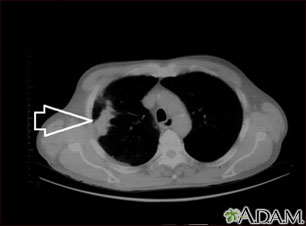

- When a tumor or mass (clump of cells) is suspected, including a solitary pulmonary nodule seen on a chest x-ray

- Lung cancer or cancer that has spread to the lungs from elsewhere in the body

- Tumors, nodules, or cysts in the chest